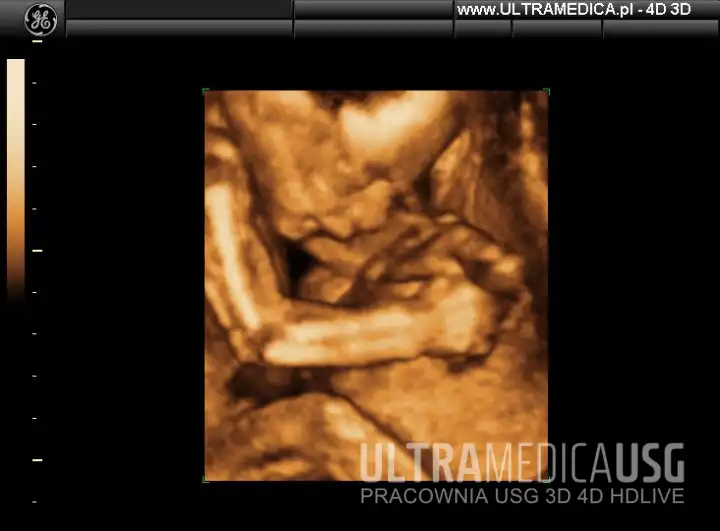

USG w 2 trymestrze – zdjęcia i filmy

Przykładowe zdjęcia i filmy z USG 2 trymestru wykonanych w gabinetach ULTRAMEDICA:

Film: Obraz przestrzenny kończyn dolnych u dziecka 20 tydzień

Oglądanie zdjęć i filmów z USG ciąży to niezwykłe przeżycie, które umacnia więź rodziców z rozwijającym się dzieckiem.

Na Twoja prośbę lekarz nagra fragment filmu z USG, który możesz zabrać do domu i pokazać go innym osobom.